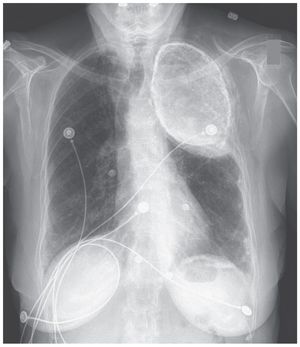

An 86-year-old woman with hypertension presents with epigastric pain and does not report any respiratory symptoms. Her chest radiograph demonstrates these findings. What is the diagnosis? Oleothorax Hemothorax Calcified empyema Non-small-cell lung cancer Asbestosis

An 86-year-old woman with hypertension who had been treated for pulmonary tuberculosis in the 1950s presented with burning chest and epigastric pain. She had no respiratory symptoms. After acute coronary syndrome was ruled out, she was treated for gastroesophageal reflux, which relieved her symptoms. A chest radiograph showed a dense opacity in the upper area of the left lung. The differential diagnosis for this abnormality includes an old calcified empyema, hemothorax, and oleothorax. Given her history of treatment for tuberculosis, the most likely diagnosis was oleothorax — a treatment for pulmonary tuberculosis, abandoned long ago, that involved the instillation of oil into the pleural space to collapse the involved lung. Typically, after treatment, which could last up to 2 years, the oil was aspirated. However, asymptomatic patients were sometimes lost to follow-up and the oil was left in place, as occurred in this patient. Long-term complications, including superimposed infection and airway obstruction, have been reported. This patient had no complications or symptoms related to oleothorax.